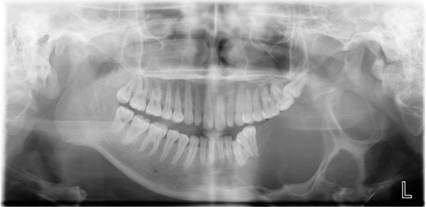

常规开展:数字化根尖片/横断牙合片、数字化口腔曲面体层片、头影测量侧位/正位片、手腕骨片、颅颌面CBCT、牙齿CBCT的检查以及涎腺造影、窦道 瘘管造影。

数字化口腔曲面体层片